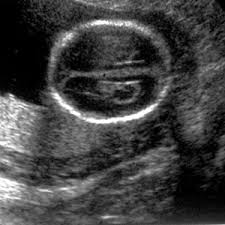

Soft Markers Of Chromosomal Aberrations Radiology Key